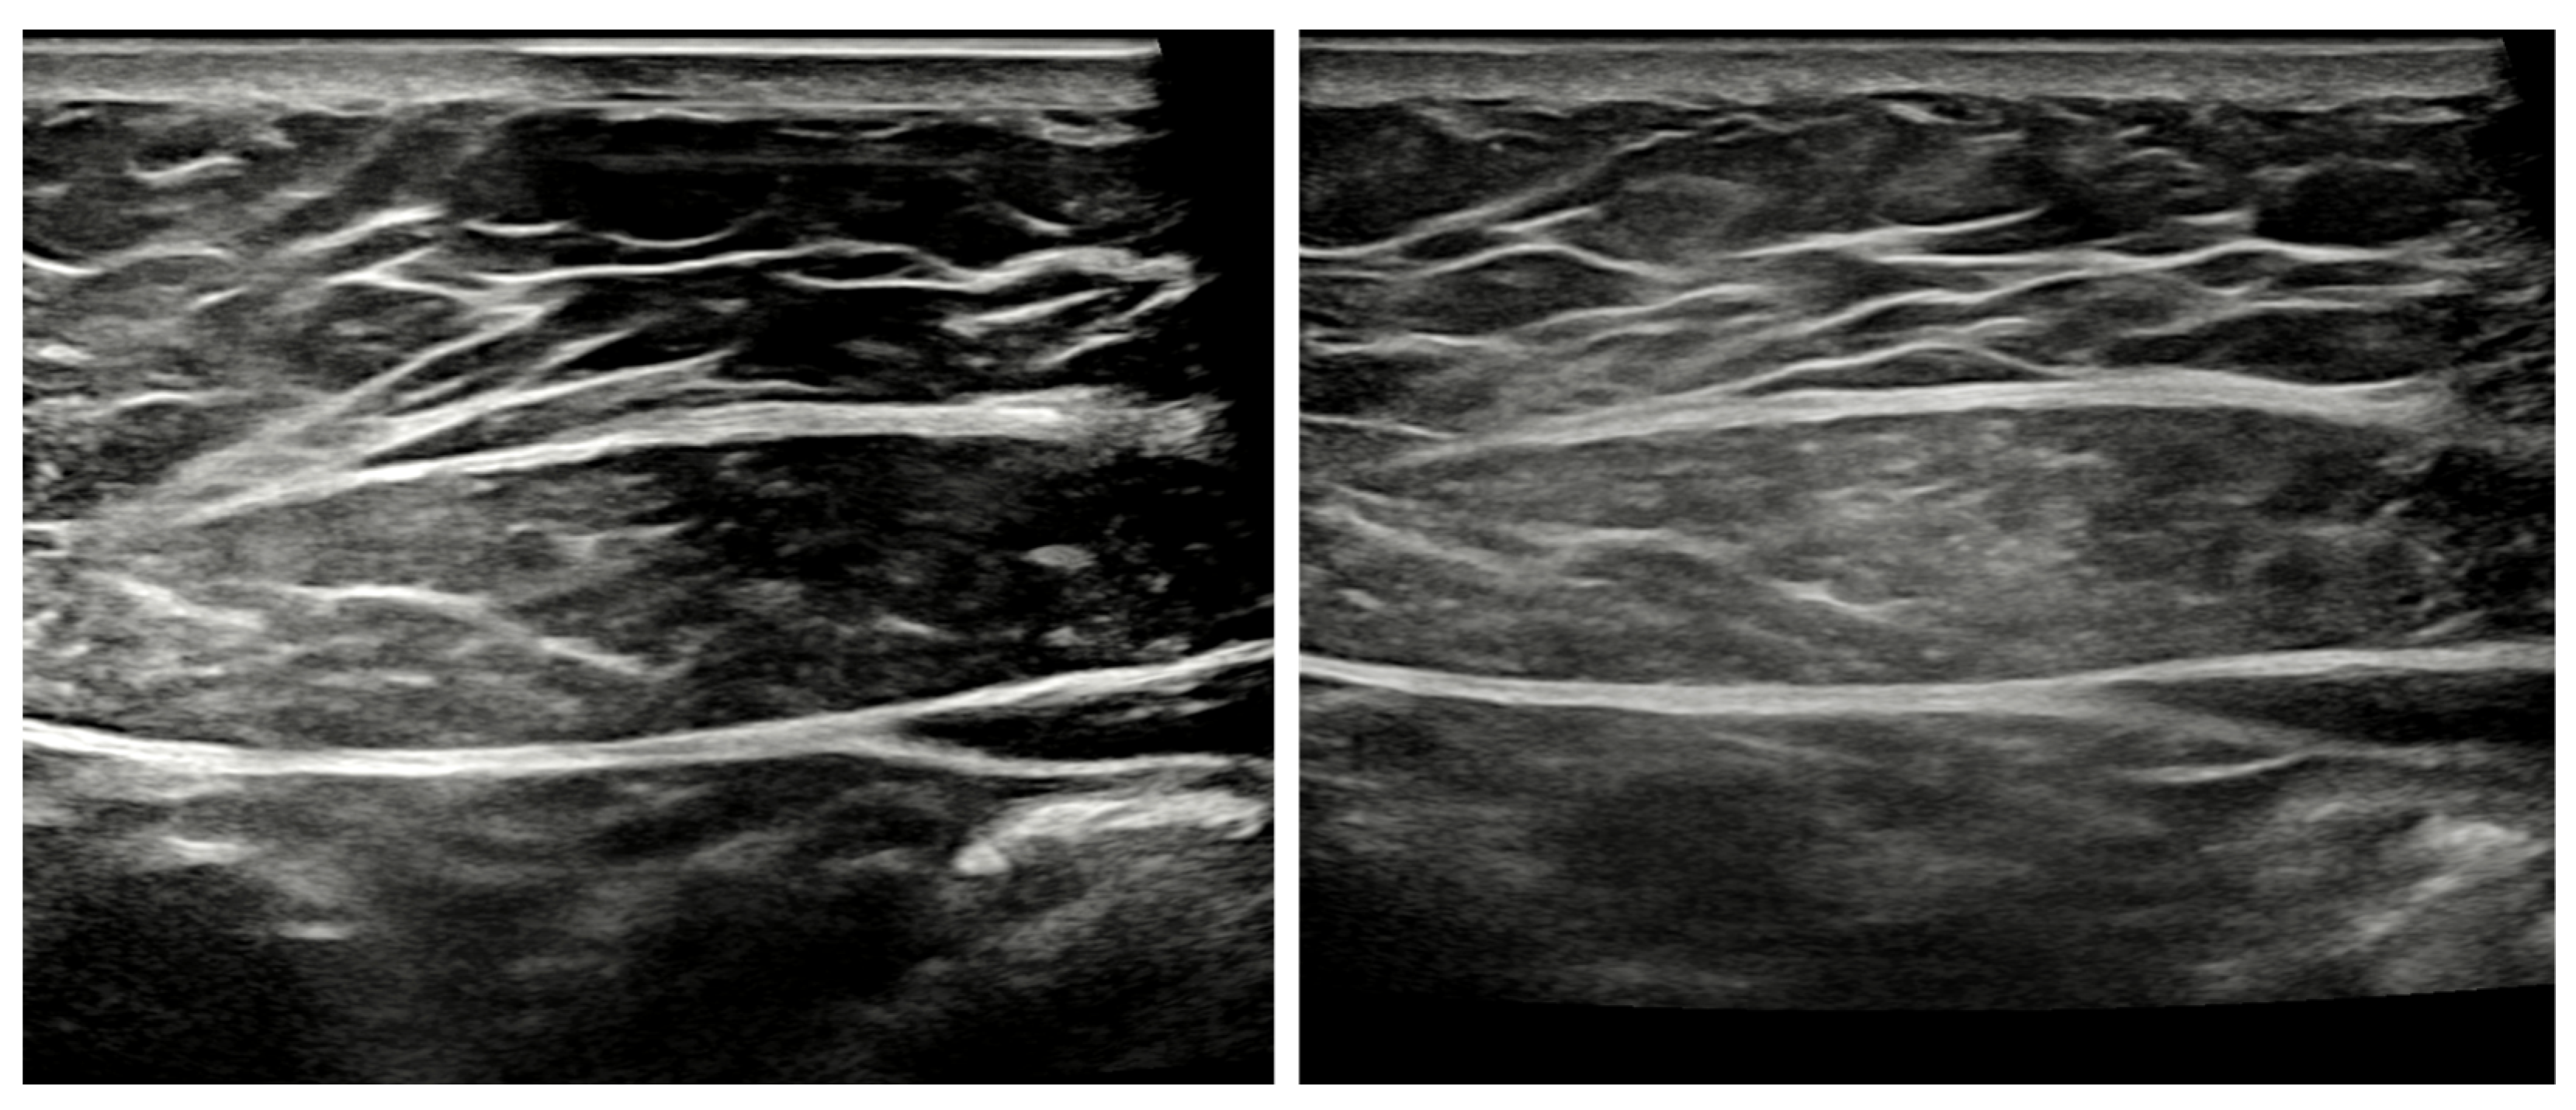

Effects of Polyurethane Absorber for Improving the Contrast between Fascia and Muscle in Diagnostic Ultrasound Images

3. Results